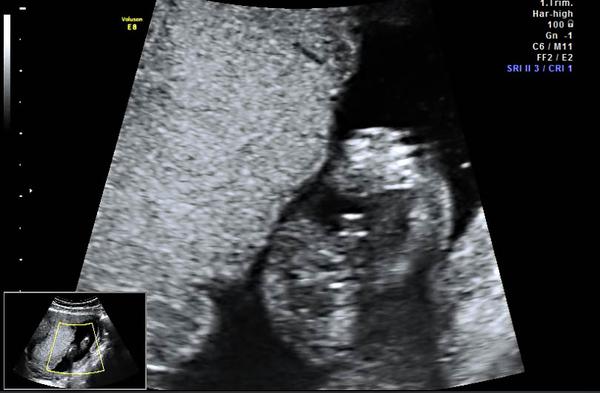

AHOJ, PRIKLADAM DVE FOTECKY ZE SCREENINGU.. OBE 13 + 1... PRVNI FOTO JE NAS DVOULETY CHLAPECEK.. JE VIDET VYBEZEK NAHORU, DRUHE FOTO , JE MIMINO, KTERE MAM TED V BRISKU.. DLE LEKARKY TO VYPADA NA HOLCICKU.. A JA ZATIM ASI MOHU SOUHLASIT..... NA DRUHE FOTCE VYBEZEK NAHORU NENI.... TAK OPET UVIDIME ZDA MI TO MA LEKARKA ZA TRI TYDNY POTVRDI...